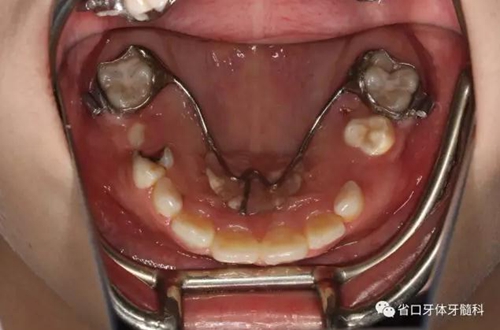

口內(nèi)情況:牙合 面觀